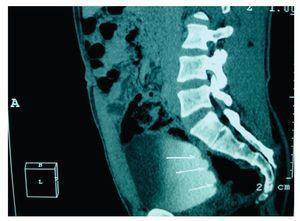

La nefrotomografía simple resultó muy dudosa a la presencia del cálculo referido en el ultrasonido anterior. El análisis general de orina reportó algunas bacterias, uno a dos eritrocitos por campo y huellas de proteínas. Se le solicitó URO-TAC, que demostró microlitiasis renal derecha del cáliz medio, no obstructivo, de aproximadamente tres milímetros. Además de pólipos vesicales múltiples (Imágenes 1 y 2).

Imagen 2. En esta proyección, y señalado por las flechas, se evidencian tres tumoraciones en la vejiga, que demuestran los defectos de llenado.